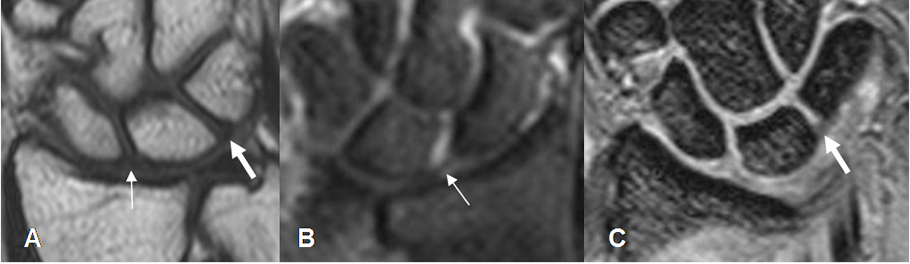

Los ligamentos también son bien estudiados con la RM. El grupo de intrínsecos es mejor visualizados en secuencias coronales y los extrínsecos en cortes sagitales. (4). Se identifican como estructuras delgadas, con baja señal de intensidad (SI) en todas las secuencia, adyacente a estructuras óseas y rodeados por grasa. (Fig 24 a 27).

Fig 24. Ligamentos intrínsecos normales.

A: RM coronal en T1, B: RM coronal en STIR y C: RM coronal en GE.

Ligamento escafolunado (Flecha delgada) y ligamento semilunopiramidal (Flecha gruesa).

Fig 25. Ligamentos extrínsecos anteriores normales.

A: RM coronal en GE Ligamento radioescafoideo.

B: RM coronal en T1. Ligamento radiolunopiramidal.

Fig 26. Ligamentos extrínsecos posteriores normales.

A: RM coronal en T2. Ligamento radioescafoideo.

B: RM coronal en GE. Ligamento radiolunado.

C: RM coronal en T2. Ligamento radiopiramidal.